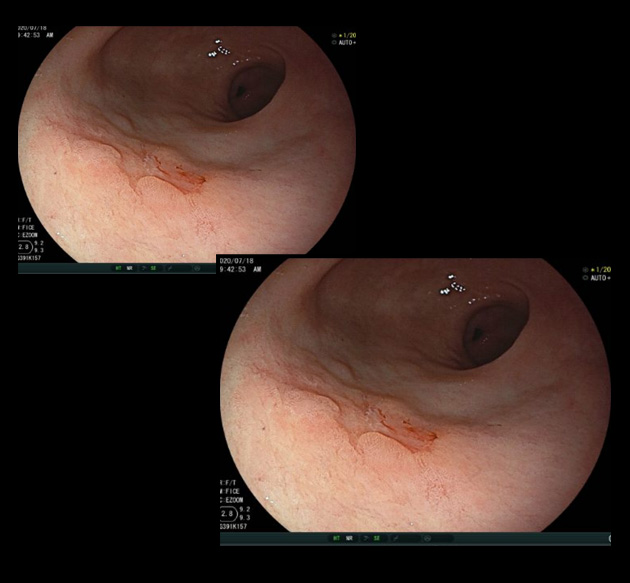

단 한 번의 내시경 검사로, 위암을 진단 못할 수도 있습니다. 위통이나 속 쓰림, 소화불량 등의 증상이 있고 위암일 가능성이 조금이라도 있다면 다시 위내시경을 시행하여 확인하는 것이 중요합니다. 위내시경 시행 후 괜찮다고 안심하지 마시고, 증상이 지속되거나, 위암의 고위험군이라면 지속적인 위내시경 검사를 하시는 것이 좋습니다.